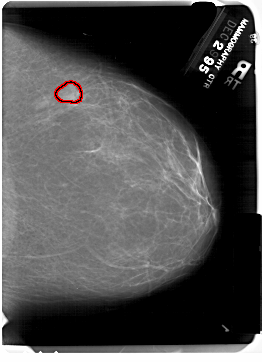

A_1372_1.RIGHT_MLO

RIGHT_MLO LINES 6871 PIXELS_PER_LINE 4891 BITS_PER_PIXEL 12 RESOLUTION 43.5 OVERLAY

FILE: A_1372_1.RIGHT_MLO.OVERLAY

TOTAL_ABNORMALITIES 1

ABNORMALITY 1

LESION_TYPE MASS SHAPE LOBULATED MARGINS OBSCURED

ASSESSMENT 4

SUBTLETY 3

PATHOLOGY BENIGN

TOTAL_OUTLINES 1

BOUNDARY